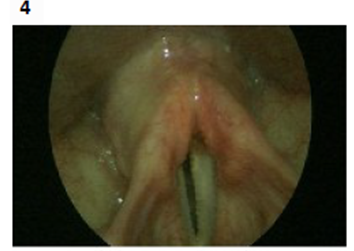

Endoscopic vocal cord examination pictures (one year after the injury) as shown down:

Lt vocal cord weakness with thickening post augmentation. Figures